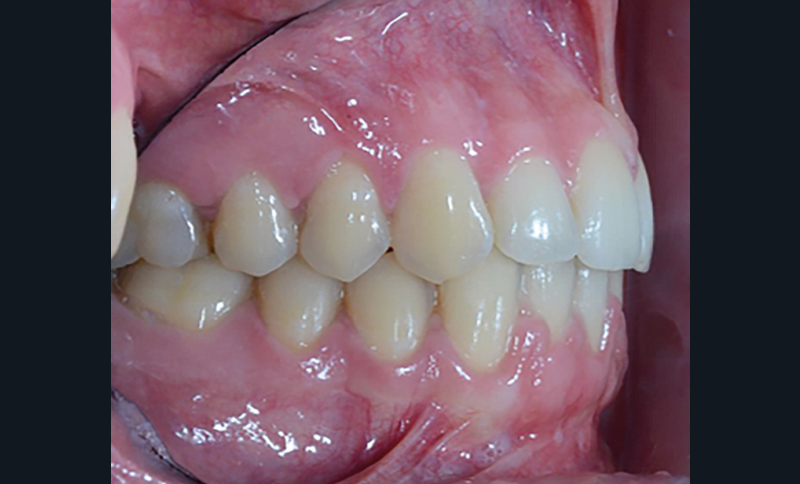

C’est à ces questions que nous permettront de répondre les deux premiers conférenciers, parodontologistes : le Dr Béatrice Straub nous présentera le renfort parodontal minéralisé, technique qu’elle a développée et pratique depuis de nombreuses années, pour éviter les préjudices des mouvements orthodontiques à risque, notamment lors des décompensations préchirurgicales (fig. 1a-d) ; le Pr Anton Sculean abordera le thème des greffes, avec leurs indications, les différentes techniques à privilégier et illustrera ses propos par de nombreux cas cliniques aux résultats esthétiques impressionnants.